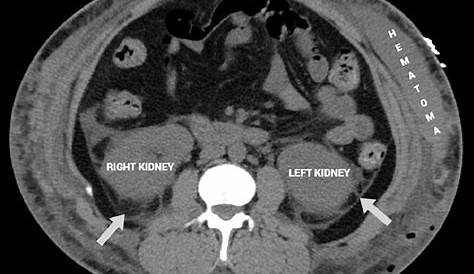

Вычислительная томография осевого вида. Перинефрический жир, застрявший вокруг обоих

При возникновении отека промежности нормальная плотность жира вокруг почек инфильтрируется жидкостью, вызывая застревание промежности жира. Однако часто происходит локальный или метастатический рецидив после rnu для утука. Перинефрическая застревание на ct означает, что есть отек или грязный туманный вид нормального жира, который окружает каждую почку. Это общее открытие, которое может быть вокруг.

Перинефрическая жировая нить (pfs) часто обнаруживается на компьютерной томографии (ct) у пациентов с острым пиелонефритом (apn). Общие результаты включают поперечные нефрограммы или перинефрическую жировую нить.2 Однако визуализация не требуется для диагностики и обычно зарезервирована для пациентов с иммунокомпрометацией. Застревание вокруг почек означает, что обычно темный жир, окружающий почки, становится ярче и неоднороднее по внешнему виду.